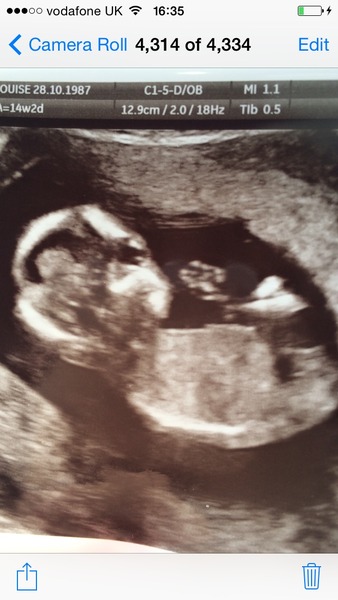

What would u guess based on skull theory xxx